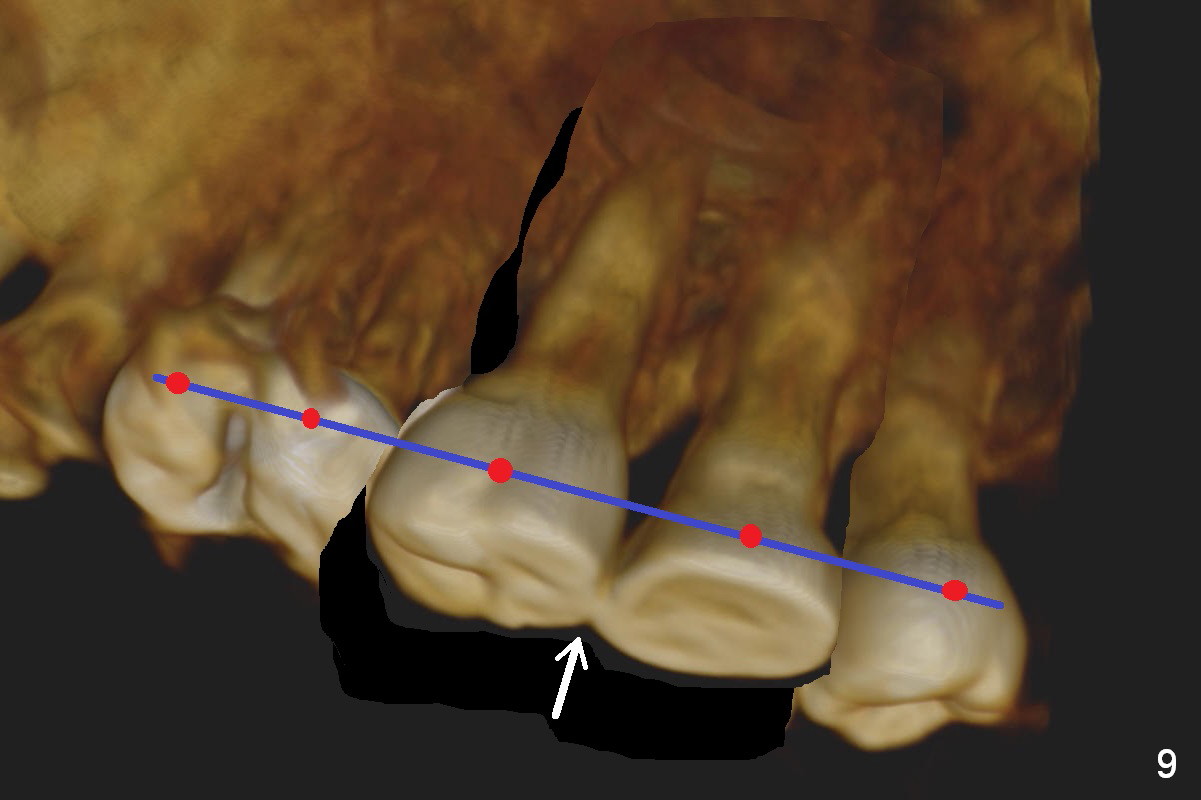

Fig.8 is a preop palatal view of the region. When the segment is lift (Fig.89 arrow), use a twisted wire (lingual retainer; blue line) and composite (red dots) for fixation. The splint may be also used for fixation. On the right, use a thin ortho wire to tighten the splint against mini implants, while on the left, thin ortho wire and composite will be used. The patient will eat soft diet for several months. Keep good oral hygiene.